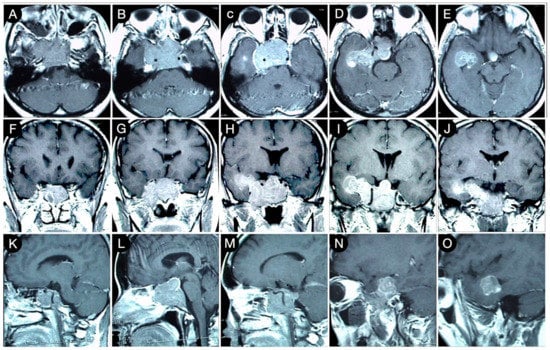

3.2.2. Case #3: Paramedian Pattern of Growth with Parenchymal Invasion

3.3.1. Case #4: Involvement of the Middle Skull Base with Parenchymal Invasion

3.3.2. Case #5: Extension beyond the Lateral Wall of the Cavernous Sinus

3.3.3. Case #6: Encasement of the Posterior Communicating and Anterior Choroidal Artery

Case #7: Encasement of the Paraclinoid and Supraclinoid Internal Carotid Artery

Case #8: Aggressive ACTH Tumor with Multiple Recurrences